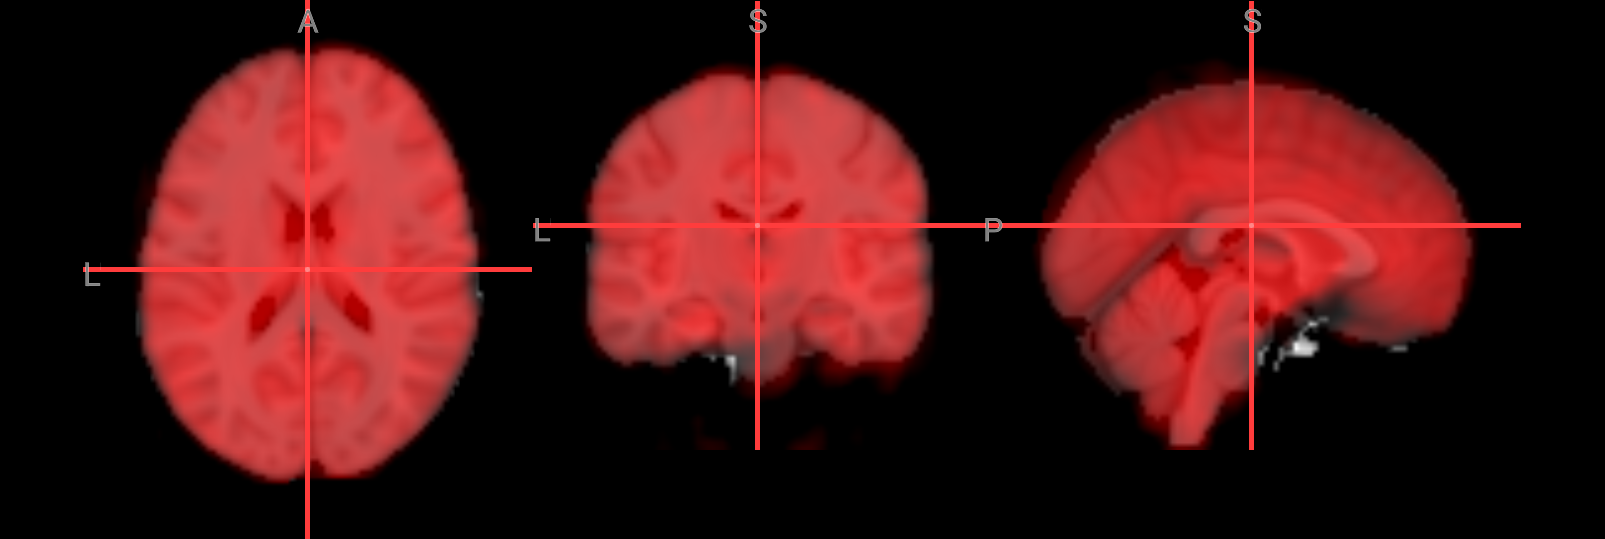

Visualization of the brain extracted image#

Check the following overlay image for areas where too much brain tissue has been removed or where parts of the skull haven’t been fully stripped away. The goal is to produce an image where the skull and face are completely removed, leaving only the brain—cortex, subcortical structures, brainstem, and cerebellum—intact.

# Visualize the skull-stripped (red) on top of the original T1 anatomical image

nv.load_volumes([

{"path": "./ds000102/sub-08/anat/sub-08_T1w.nii.gz", "name": "T1w", "colormap": "gray"},

{"path": "./FSL_preproc/sub-08_T1w_brain.nii.gz", "name": "T1w_brain", "colormap": "red", "opacity": 0.5}

])

nv

Image(url='https://raw.githubusercontent.com/NeuroDesk/example-notebooks/refs/heads/main/books/images/fsl_preproc_bet_05.png')